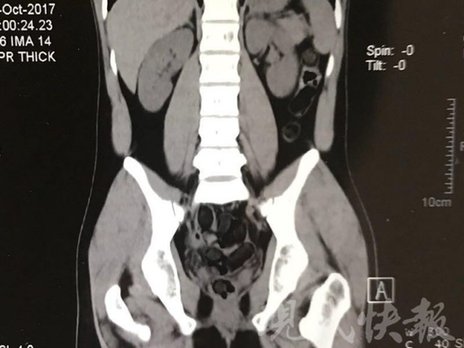

小伙體內(nèi)藏毒300余克 CT掃描圖密密麻麻

運(yùn)毒小伙:希望被判處死刑

由于毒品在體內(nèi)一旦泄露有可能致命,警方第一時(shí)間將阿永帶到醫(yī)院進(jìn)行檢查。CT 掃描的結(jié)果顯示,阿永體內(nèi)布滿(mǎn)了密密麻麻的白色圓柱狀固體,就像一粒粒的蠶蛹。在南京市公安局鼓樓分局二板橋派出所,阿永分四次排出了毒品,毛重369.99克。經(jīng)訊問(wèn),阿永交代了自己全部的犯罪事實(shí)。目前,阿永已被刑事拘留。